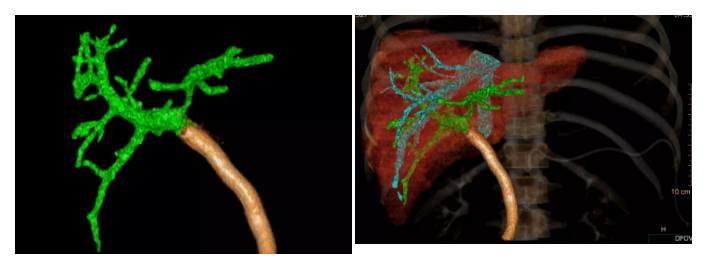

数字化血管三维成像:(1)胰腺头颈部及相邻体部囊实性肿瘤,考虑实性假乳头状瘤可能大,相邻血管及十二指肠明显受压,门静脉主干旁个别淋巴结肿大;(2)副脾;(3)双肾多发囊肿

术后上腹部增强CT血管重建显示门静脉通畅,肝脏血供良好